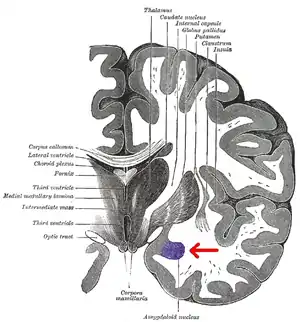

![]() Subdivisions of the amygdala | |

The amygdala (/əˈmɪɡdələ/; pl.: amygdalae /əˈmɪɡdəli, -laɪ/ or amygdalas; also corpus amygdaloideum; Latin from Greek, ἀμυγδαλή, amygdalē, 'almond', 'tonsil'[1]) is a paired nuclear complex present in the cerebral hemispheres of vertebrates. It is considered part of the limbic system.[2] In primates, it is located medially within the temporal lobes.[3] It consists of many nuclei, each made up of further subnuclei. The subdivision most commonly made is into the basolateral, central, cortical, and medial nuclei together with the intercalated cell clusters.[4] The amygdala has a primary role in the processing of memory, decision-making, and emotional responses (including fear, anxiety, and aggression). The amygdala was first identified and named by Karl Friedrich Burdach in 1822.[5]

Over a dozen nuclei have been identified, each with their own subdivisions and distinct connections to the rest of the brain.[6] The chief nuclei are the basolateral complex, the central nucleus, the cortical nucleus, the medial nucleus, and the intercalated cell clusters.[4]